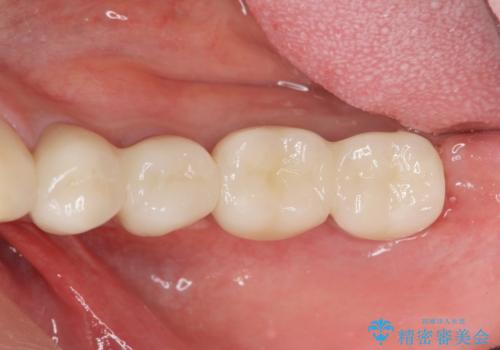

部分的な治療ではなく、全体的な治療を任せていただけたことで、清掃性の高く咬合関係の良い治療を行うことができました。

見た目の改善だけでなく、噛み合わせの仕上がりにも大変満足いただくことができました。